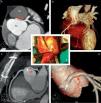

Anomalía coronaria congénita, un enemigo silencioso del ejercicio físico

Congenital coronary anomaly, a silent enemy of exercise